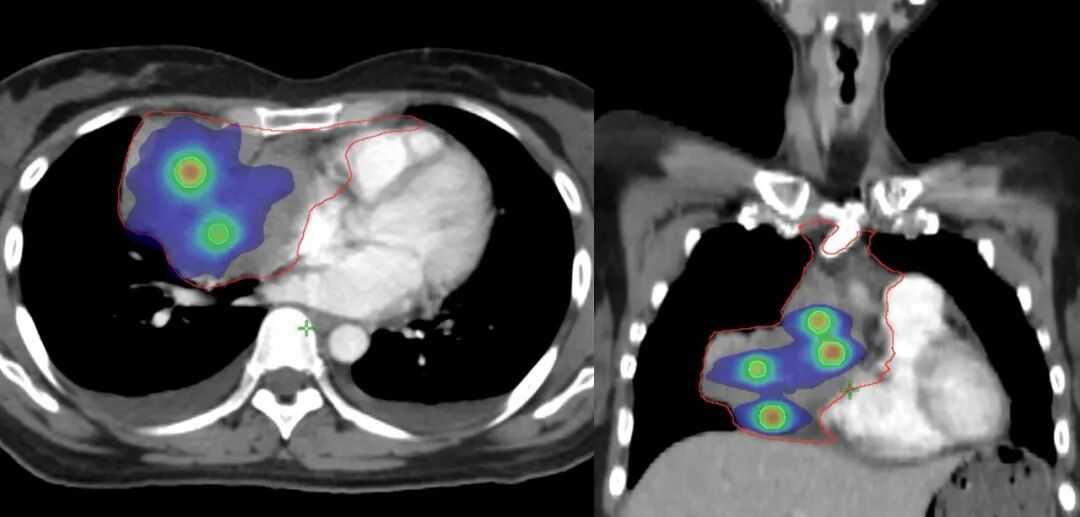

圖注:放射治療靶區(qū)及劑量分布圖。紅線是放射治療靶區(qū);綠色球體為放射治療高劑量分布,可見聚焦照射,周邊劑量快速跌落,周圍組織受到良好保護。